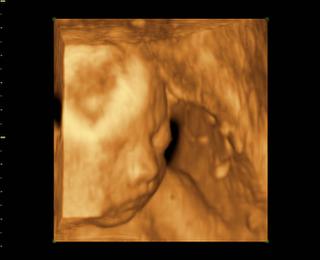

@bv_alexandra 3Dčko je skôr pre potešenie, morfologický UV je na diagnostiku, vidno na ňom orgány a kosti bábätka, vidno chlopne srdiečka, je možné zmerať dĺžku kostí a tak podobne, len pre porovnanie, už som to sem dávala aj predtým a písala som o tom, pridávam ti fotky z môjho prvého tehu, tie "farebné" sú z 3Dčka tam je krásne vidieť bábätko, tváričku, črty tváre, je vidieť na koho sa podobá, ako vyzerá, na morfologickom, to je ten čiernobiely vidieť bábo "zvnútra" aby sa potvrdilo že je úplne zdravé a nemá žiadne vývojové vady, podľa dĺžky kostí ti tam aj spresnia termín pôrodu.